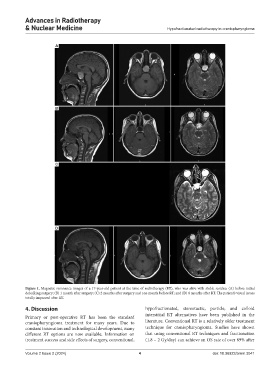

Figure 1. Magnetic resonance images of a 17-year-old patient at the time of radiotherapy (RT), who was alive with stable residue: (A) before initial

debulking surgery; (B) 1 month after surgery; (C) 2 months after surgery and one month before RT; and (D) 8 months after RT. The patient’s visual issues

totally improved after RT.